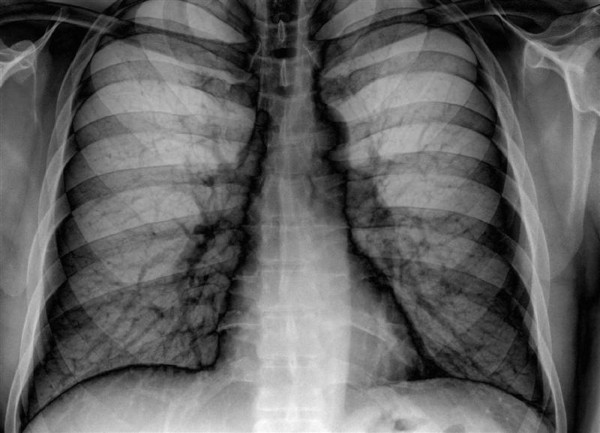

Το σύστημα τεχνητής νοημοσύνης της Google Health μπορεί να μελετήσει ακτινογραφίες πνευμόνων και να βγάλει συμπεράσματα εξίσου αξιόπιστα με εκείνα των έμπειρων ακτινολόγων.

Οι ερευνητές, που έκαναν τη σχετική δημοσίευση στο επιστημονικό περιοδικό Radiology της Ακτινολογικής Εταιρείας της Βόρειας Αμερικής, εκπαίδευσαν το σύστημά τους τροφοδοτώντας το με περισσότερες από 860.000 ακτινογραφίες. Η ακτινογραφία πνευμόνων είναι από τις συχνότερες εξετάσεις παγκοσμίως, όμως έχει ορισμένους περιορισμούς.«Βρήκαμε ότι υπεισέρχεται σε μεγάλο βαθμό ο υποκειμενικός παράγοντας στην ερμηνεία της συγκεκριμένης ακτινογραφίας, κάτι που περιορίζει την αποτελεσματικότητά της», ανέφερε ο επικεφαλής ερευνητής της Google Health, Σράβια Σέτι.

«Η ερμηνεία των ακτινογραφιών των πνευμόνων συχνά γίνεται με υποκειμενικό τρόπο, κάτι προβληματικό από την οπτική γωνία της βαθιάς μάθησης. Καταφέραμε να παράγουμε ένα σύστημα που κάνει πιο αξιόπιστη αξιολόγηση», δήλωσε ο συνάδελφός του, Ντάνιελ Τσε.

Οι δοκιμές του συστήματος από επιτροπή ακτινολόγων έδειξαν ότι τα καταφέρνει τουλάχιστον εξίσου καλά με τους γιατρούς στην ανίχνευση διαφόρων προβλημάτων (διάγνωση καταγμάτων, οζιδίων, όγκων, πνευμοθώρακα κ.ά.).